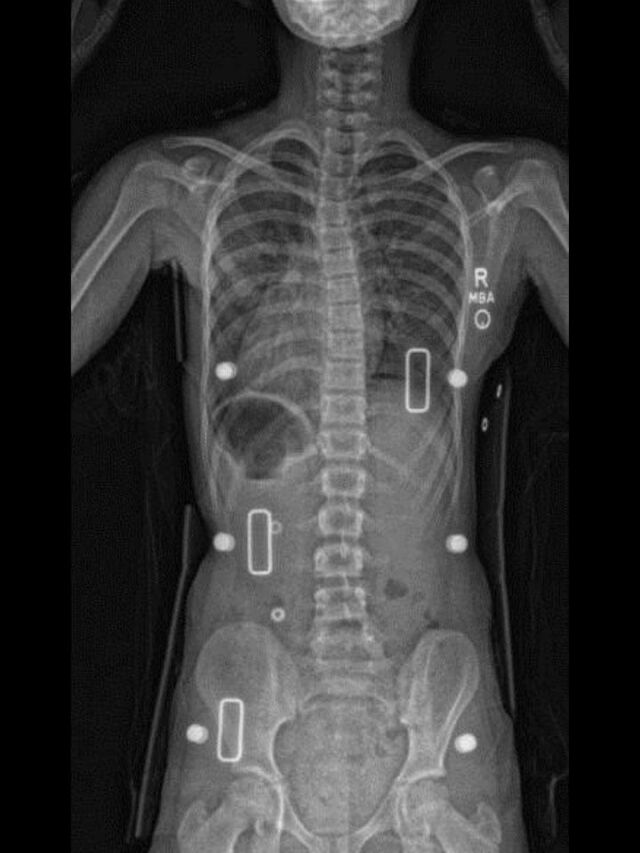

The Boston (Style) scoliosis orthosis is a TLSO designed to slow the progression of scoliosis in growing spines. The brace has been clinically proven to control curve progression in the Lumbar, Thoracic, and Thoracolumbar spinal curves. This orthosis is effective for the treatment of (AIS) Adolescent Idiopathic Scoliosis.

Using the patient's x-rays to define the spinal curve presented, the brace is fabricated custom to measurements, scan or cast taken and is custom fit for each individual patient.

- Finished to x-rays provided.